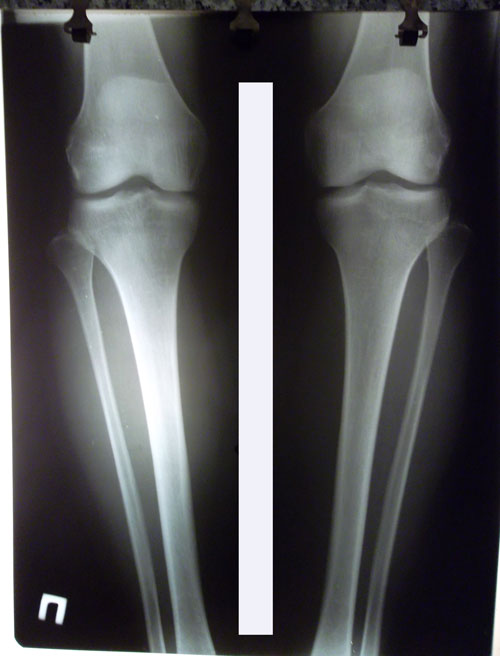

рентген до операции.